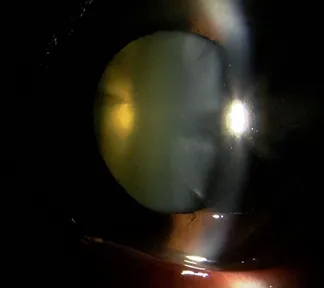

白内障とは

目の中のレンズである水晶体が濁って、見えにくくなることを白内障といいます。濁る原因の多くは加齢によるもので、誰にでもいつかは起こります。その他に、糖尿病や薬の影響で白内障になることもあります。ふつう濁りは急に進行することはありませんが、一度濁ってしまった水晶体は残念ながら元には戻りません。症状の軽いうちは、生活にそれほど問題はありませんが、ものが見えにくくなり、生活にも不自由を感じるようになれば、手術をする必要があります。